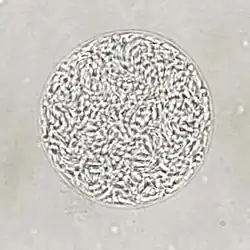

| Giemsa stained T. gondii tachyzoites, 1000× magnification | |

Tachyzoites

Motile, and quickly multiplying, tachyzoites are responsible for expanding the population of the parasite in the host.[47][30]: 19 When a host consumes a tissue cyst (containing bradyzoites) or an oocyst (containing sporozoites), the bradyzoites or sporozoites stage-convert into tachyzoites upon infecting the intestinal epithelium of the host.[30]: 359 During the initial acute period of infection, tachyzoites spread throughout the body via the blood stream.[30]: 39–40 During the later, latent (chronic) stages of infection, tachyzoites stage-convert to bradyzoites to form tissue cysts. To survive in the host, tachyzoites manipulate the immune response by injecting the contents of rhoptries into host cells. This seems to be vital for their survival, as knock-out strains of T. gondii which are unable to inject hosts with rhoptries have been shown to be avirulent in vivo.[29]